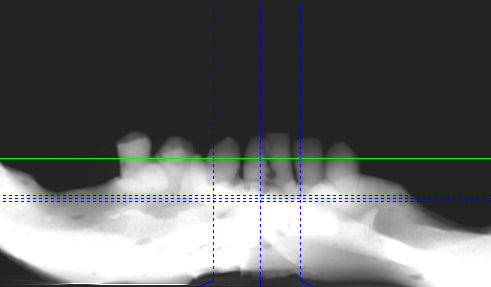

j'ai fais plusieurs tentatives avec mon cone beam avant d'avoir un réglage correct

c'est bien pour cela que quand on dispose d'un cone beam, ça aide beaucoup....

j'ai essayé de scanner un modèle en plâtre avec mon cone beam Gendex CB-500 et ça donne cela

pas mal growler...

mais je doute que la précision soit suffisante pour avoir un repositionnement précis et surtout stable du guide en bouche...

sans faire de pub pour un cone beam (ce serait mieux de parler de réglages que de marques)

dam dam a bien raison , il faut régler le cone beam avec des kv au alentour de 80 et environ 3mA pour les appareils résines , .. un peu plus pour le plâtre.